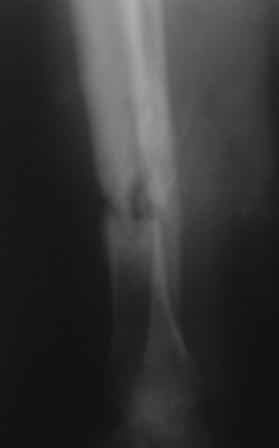

Посттравматический ложный сустав б/берцовой кости.

Добрый вечер, уважаемые коллеги! Обратилась женщина, 30 лет. ДТП 11 октября 2008 г. Из выписки: О/многооскольчатый перелом костей левой голени по Каплану 3В,

ПХО раны, гипсовая повязка, перевод в гор.б-цу, в 21.10.08г КДО аппаратом Илизарова(почему-то в вальгусном положении), ч-з два месяца тромбофлебит лев.н/конечности, отеки, воспаление, и аппарат сняли, с тех пор ходит в гипсовой повязке со стременем. к-рую периодически меняют, якобы кость со временем срастется.

На уровне н/з голени глубокие рубцы по передне-медиальной поверхности, умеренная отечность голени, незначительная патологическая подвижность, умерен. болезненность, ось правильная, укорочение 1,5см.

Наш план БИОС после остеоклазии м/берцовой кости. Но укорочение еще будет увеличиваться!